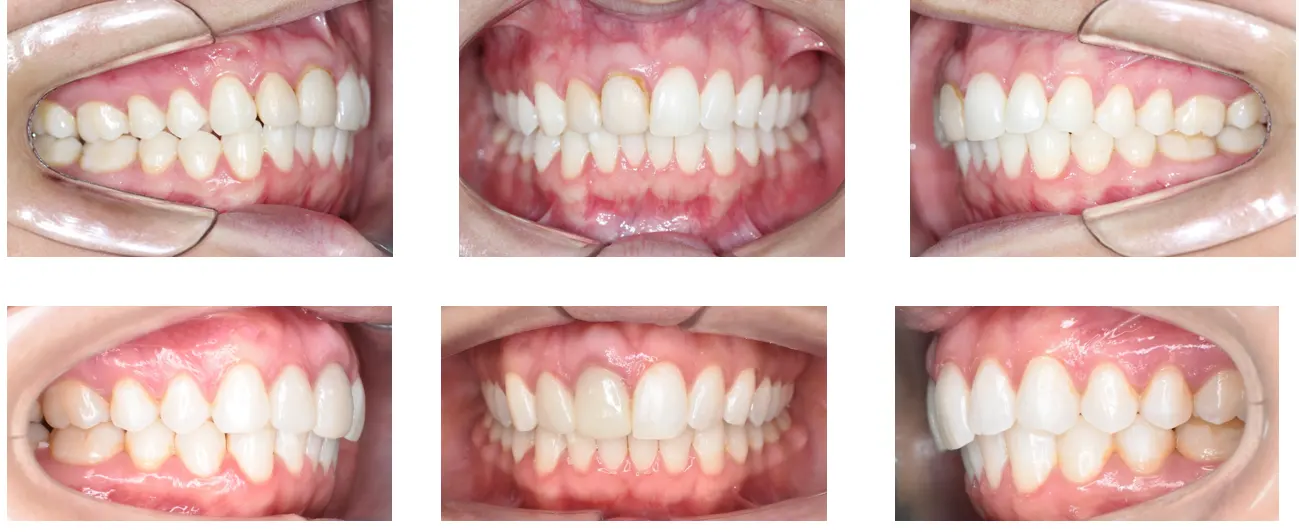

Tratamento ortodôntico com alinhadores para correção da Classe II do lado esquerdo.

O resultado foi alcançado com auxilio de mini parafuso e distalização em massa. Foi corrigido, além da Classe II, a linha média superior que estava desviada.